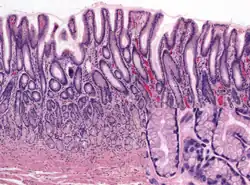

Microanatomy

Wall

Like the other parts of the gastrointestinal wall, the human stomach wall from inner to outer, consists of a mucosa, submucosa, muscular layer, subserosa and serosa.[19]

The inner part of the stomach wall is the gastric mucosa a mucous membrane that forms the lining of the stomach. The membrane consists of an outer layer of columnar epithelium, a lamina propria, and a thin layer of smooth muscle called the muscularis mucosa. Beneath the mucosa lies the submucosa, consisting of fibrous connective tissue.[20] Meissner's plexus is in this layer interior to the oblique muscle layer.[21]

Glands

The mucosa lining the stomach is lined with gastric pits, which receive gastric juice, secreted by between 2 and 7 gastric glands. Gastric juice is an acidic fluid containing hydrochloric acid and digestive enzymes.[24] The glands contains a number of cells, with the function of the glands changing depending on their position within the stomach.

Within the body and fundus of the stomach lie the fundic glands. In general, these glands are lined by column-shaped cells that secrete a protective layer of mucus and bicarbonate. Additional cells present include parietal cells that secrete hydrochloric acid and intrinsic factor, chief cells that secrete pepsinogen (this is a precursor to pepsin- the highly acidic environment converts the pepsinogen to pepsin), and neuroendocrine cells that secrete serotonin.[25]

Glands differ where the stomach meets the esophagus and near the pylorus.[26] Near the gastroesophageal junction lie cardiac glands, which primarily secrete mucus.[25] They are fewer in number than the other gastric glands and are more shallowly positioned in the mucosa. There are two kinds - either simple tubular glands with short ducts or compound racemose resembling the duodenal Brunner's glands. Near the pylorus lie pyloric glands located in the antrum of the pylorus. They secrete mucus, as well as gastrin produced by their G cells.[27]